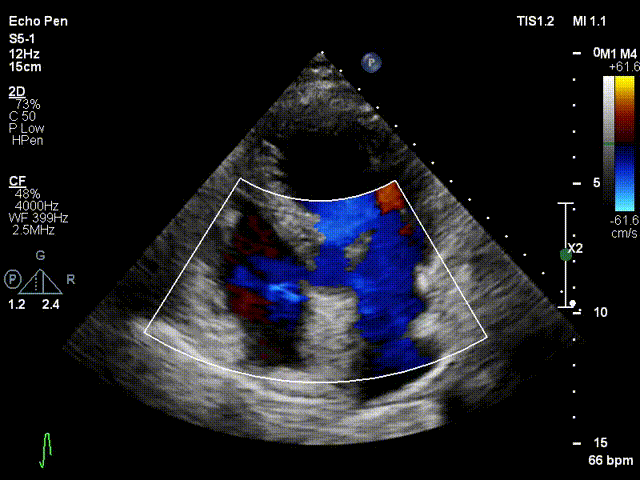

术后30天随访超声结果显示二尖瓣反流为轻度